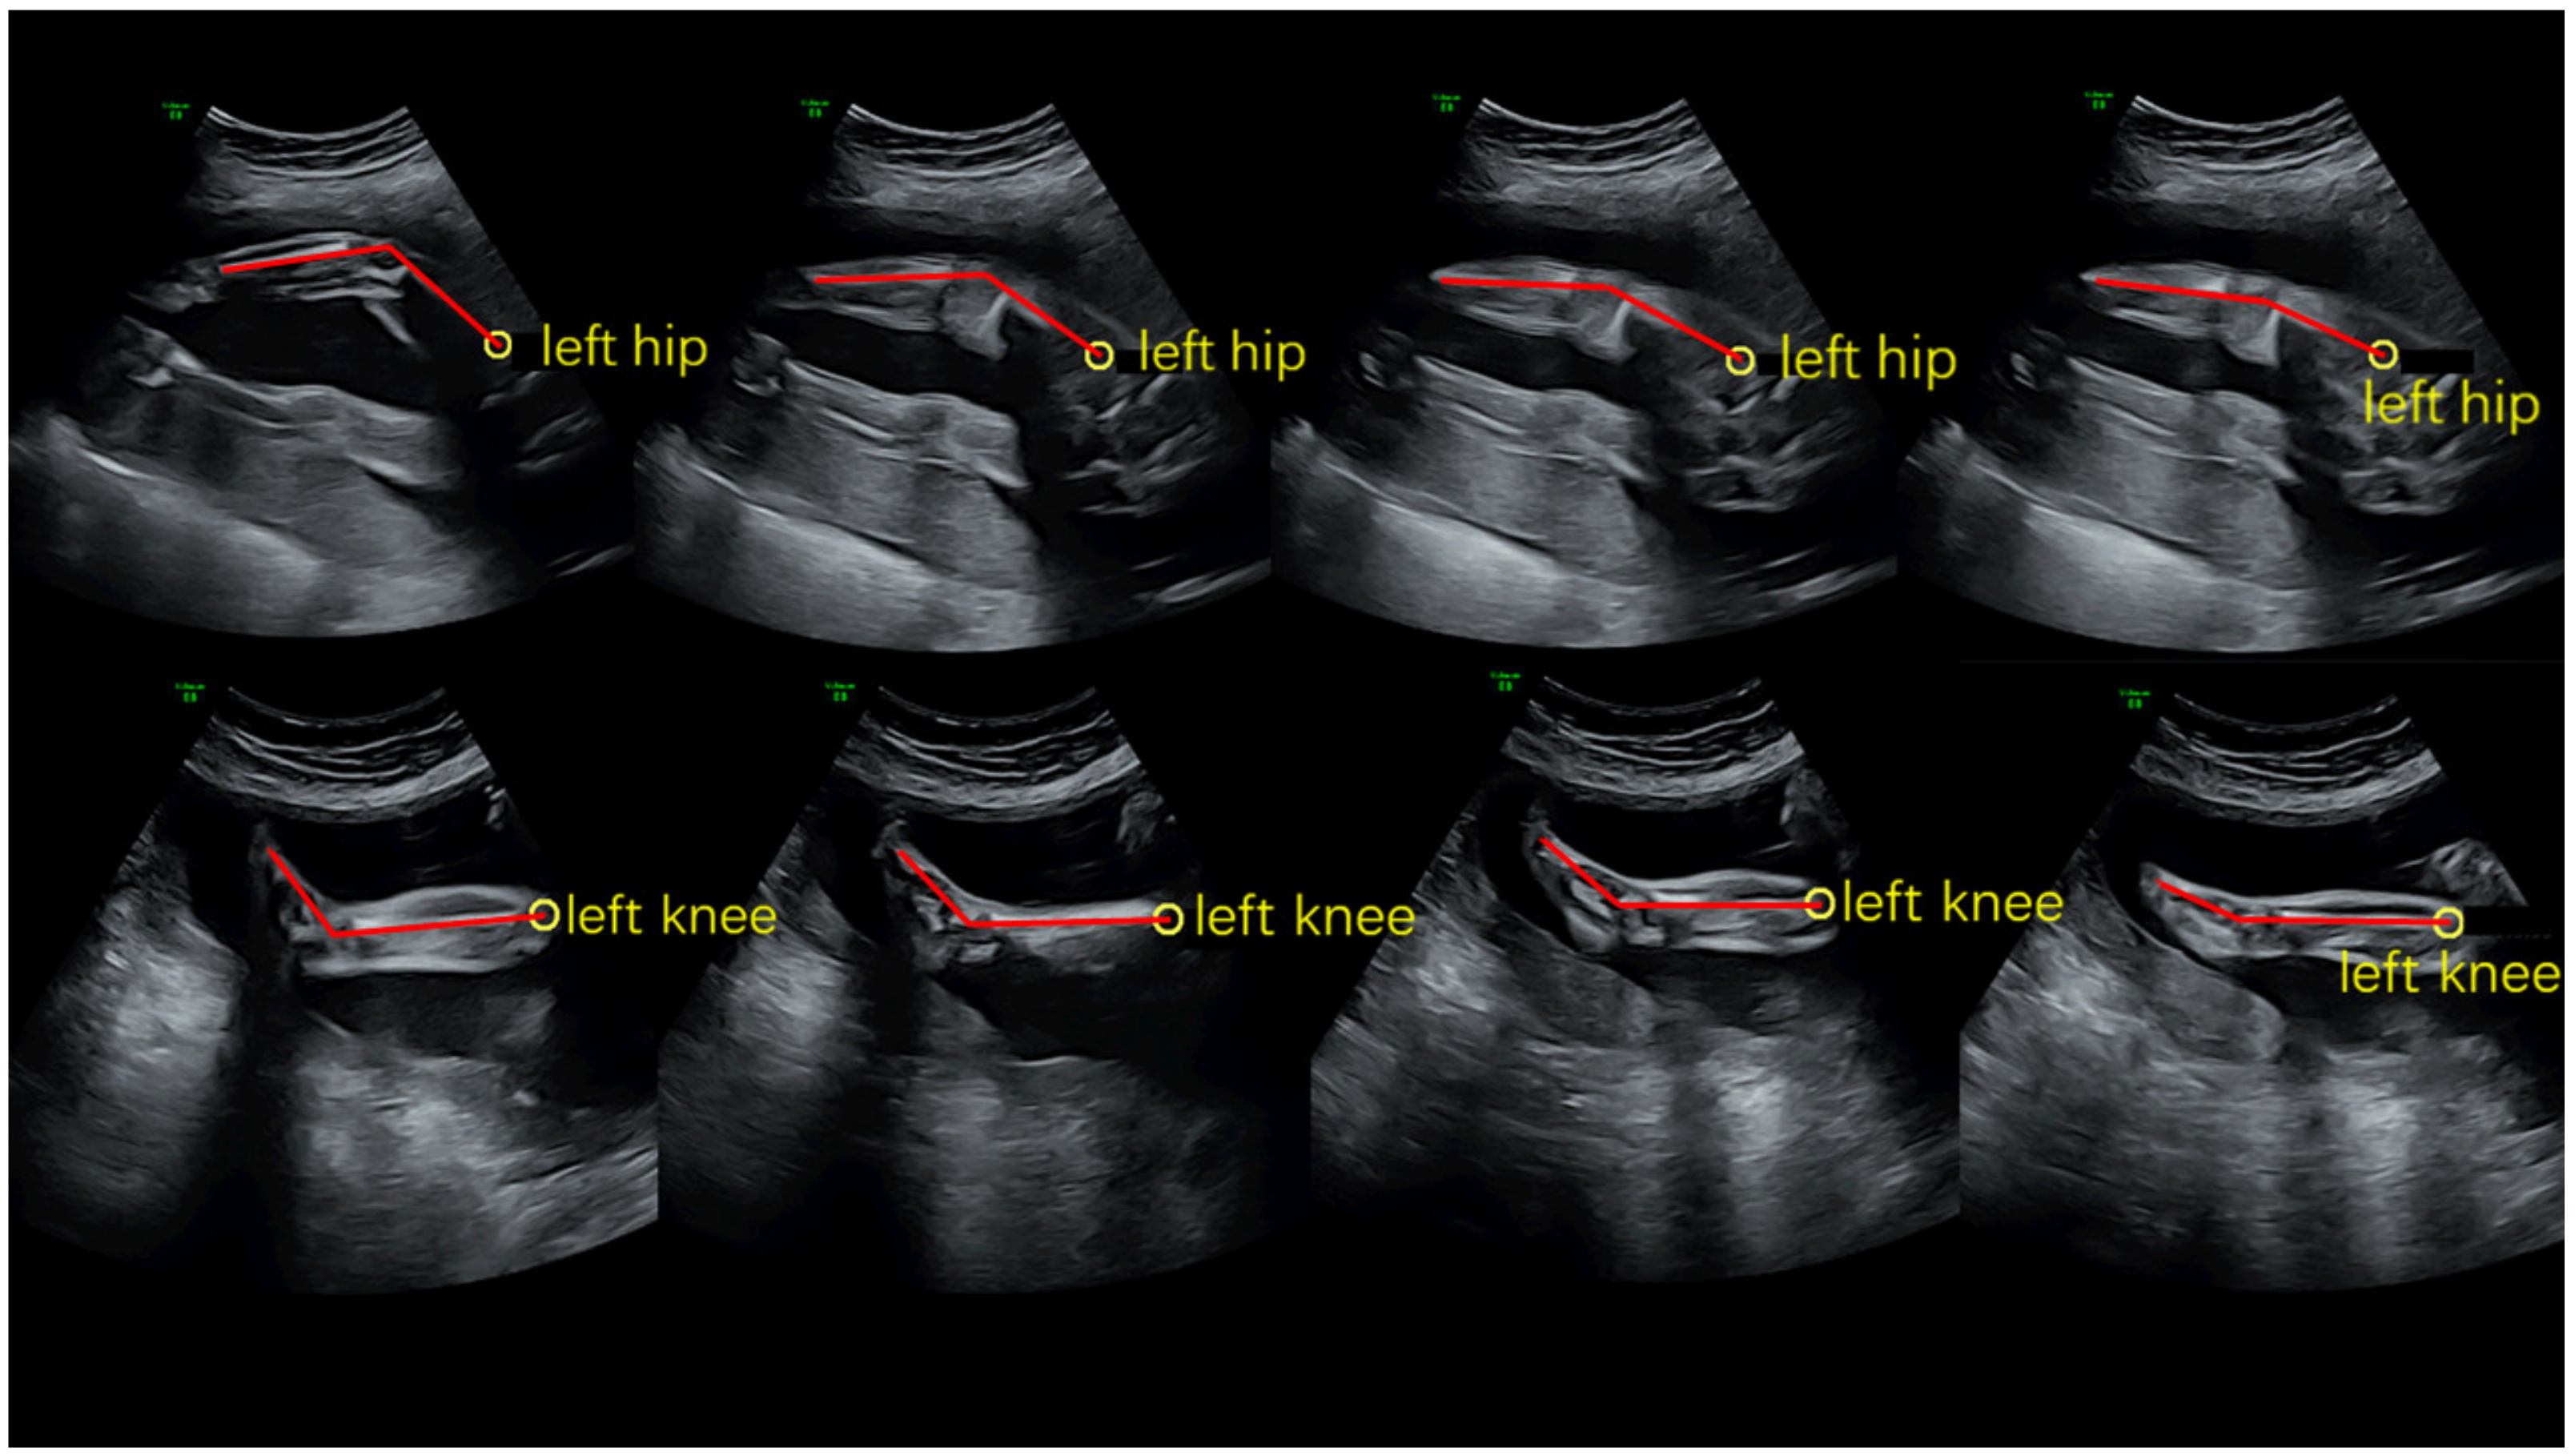

2.2. Ultrasound Scanning Processing

2.3. Kinematics Analysis Processing

2.3.1. The Angle of the Knee and Ankle Joints of the Lower Extremities